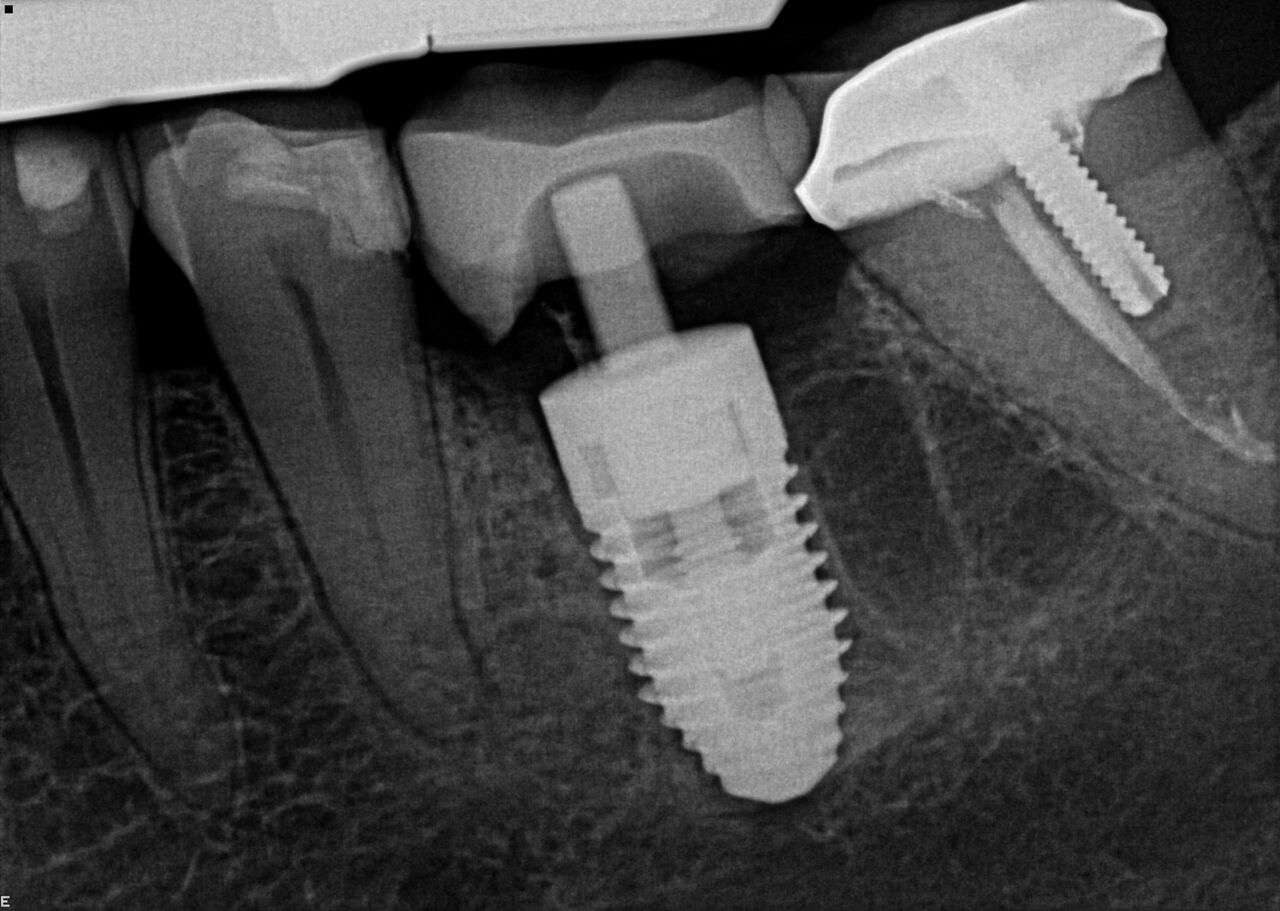

(2.) Immediate implant of No. 19 with temporization abutment.

Figure 2

(4.) Radiograph showing immediate implant of No. 19 with immediate restoration day of surgery.

Figure 4

A 63-year-old woman presented with severe pain on biting of tooth No. 19 (Figure 1). Clinically there was pain on percussion and significant periodontal probing along the mesial root. The patient was anesthetized with infiltration anesthesia and the crown was horizontally sectioned from the lingual of the tooth. The remaining tooth was sectioned so the roots could be extracted individually. The socket was fully debrided and an implant was placed (Figure 2), which was prosthetically correct and stabilized in excess of 45 Ncm. The bone was milled to allow for unimpeded placement of a temporization abutment. The initial crown was revised to be the temporary crown in infraocclusion. Cement was extruded extraorally (Figure 3) prior to seating of the temporary restoration. The socket was sealed with the temporary crown and there were no sutures or bone graft (Figure 4 and Figure 5).

The patient was instructed in postoperative care specific to an immediately provisionally restored implant and an antibiotic and analgesic was prescribed. At 4 months, integration was confirmed. The patient was impressed for a final restoration that was cemented within 2 weeks. The final radiograph (Figure 6) and clinical photo (Figure 7) presents a 1-year postoperative demonstrating good esthetics, full bone regeneration, and a steady state of bone to the implant under loading.